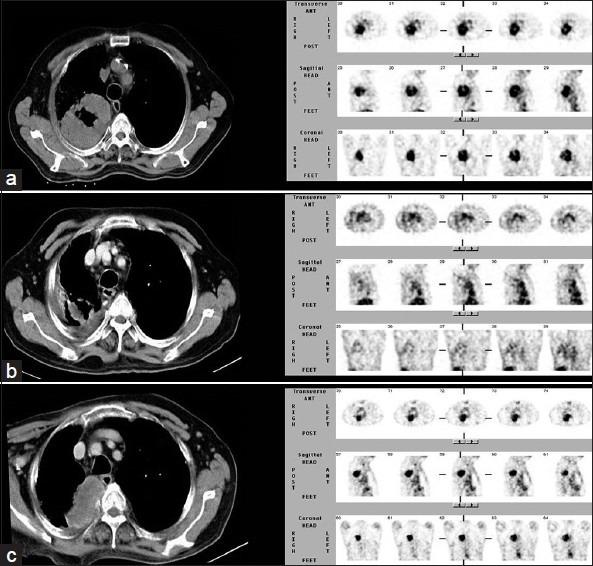

Several radiotracers have been used for assessing cell death, whether by necrosis or apoptosis. (99m)Tc glucarate, which has initially been reported to be concentrating/accumulating in myocardial infarction or zones of cerebral injury, has also shown some tumor-seeking properties in a few preliminary studies. Under International Atomic Energy Agency (IAEA)'s coordinated research program, we report here the standardization, quality control, and clinical evaluation (detection, evaluation of response, and comparison with (18)F Fluorodeoxyglucose) of this tracer in well-characterized lung cancer and head neck malignancies in a single-arm prospective observational study. Forty-seven patients (29 inoperable lung carcinoma and 18 head and neck malignancies) were prospectively enrolled and underwent (99m)Tc glucarate imaging [whole body planar and single-photon emission computed tomography of the region of interest] 4-5 hours after injection of 20 mCi of the radiopharmaceutical. Excellent (99m)Tc glucarate concentration was noted in the target lesion in lung cancer and head and neck malignancies. The sensitivity was found to be better in lung cancer. Avid concentration of tracer was seen in the metastatic sites. During response evaluation, the glucarate concentration correlated well with the clinical and other radiological findings. (99m)Tc glucarate showed avid concentration of tracer in the tumor, suggesting it to be a potential tumor imaging agent which can be used for detection and assessment of therapeutic response in malignancy.

几种放射性示踪剂已被用于评估细胞死亡,无论是坏死还是凋亡。(99m)锝葡糖醛酸,最初据报道其在心肌梗死或脑损伤区域浓聚/蓄积,在一些初步研究中也显示出一定的肿瘤摄取特性。在国际原子能机构(IAEA)的协调研究项目下,我们在此报告在一项单臂前瞻性观察研究中,对这种示踪剂在特征明确的肺癌和头颈部恶性肿瘤中的标准化、质量控制及临床评估(检测、反应评估以及与(18)F氟脱氧葡萄糖比较)。47例患者(29例不可手术的肺癌和18例头颈部恶性肿瘤)被前瞻性纳入研究,并在注射20毫居里放射性药物后4至5小时接受(99m)锝葡糖醛酸显像[全身平面显像及感兴趣区域的单光子发射计算机断层扫描]。在肺癌和头颈部恶性肿瘤的靶病变中观察到(99m)锝葡糖醛酸的良好浓聚。发现其在肺癌中的敏感性更好。在转移部位可见示踪剂的摄取。在反应评估期间,葡糖醛酸浓度与临床及其他影像学结果相关性良好。(99m)锝葡糖醛酸在肿瘤中显示出示踪剂的摄取,表明它是一种潜在的肿瘤显像剂,可用于恶性肿瘤的检测和治疗反应评估。